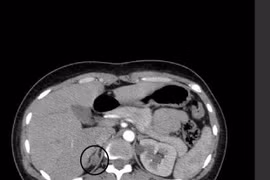

(khoahocdoisong.vn) - Nhờ sự chuyển giao kỹ thuật từ Bệnh viện Việt Đức và Bệnh viện Bình Dân, khoa Ngoại Tiết niệu - Bệnh viện Đa khoa tỉnh Thanh Hóa đã thực hiện rất nhiều kỹ thuật cao, kỹ thuật chuyên sâu chuyên ngành Tiết niệu và Nam học, cứu sống nhiều người bệnh. Một người bệnh có khối u tuyến thượng thận khổng lồ vừa được phẫu thuật thành công nhờ chuyên môn cao và thiết bị hiện đại.

U tuyến thượng thận (UTTT) là bệnh nguy hiểm không chỉ gây ảnh hưởng tới sức khoẻ, tinh thần mà còn khiến chất lượng cuộc sống giảm nghiêm trọng, dễ biến chứng tử vong. Nhờ sự chuyển giao kỹ thuật từ Bệnh viện Hữu nghị Việt Đức, Bệnh viện Đa khoa Thanh Hóa đã làm chủ kỹ thuật này, mổ cho bệnh nhân an toàn, nhanh hồi phục